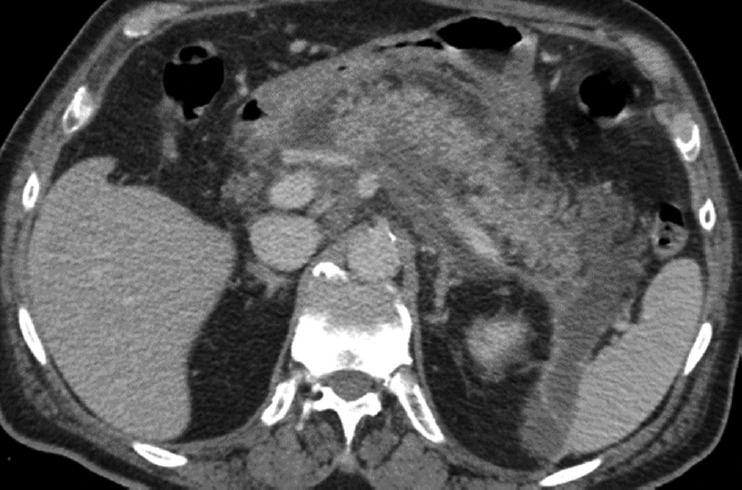

Abstract Image